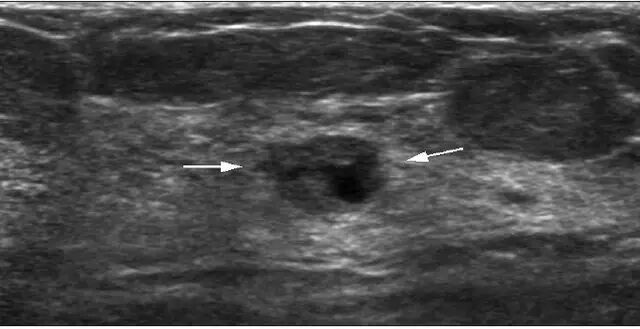

超声是乳腺检查的重要手段,有时可发现临床上无法触及且钼靶也未能显示的结节,即隐匿性乳腺结节。在这些乳腺结节中,有些结节虽然超声上存在可疑恶性征象,但穿刺病理结果却显示为良性。由于存在穿刺结果的假阴性可能,临床上对这类结节如何处置仍存在争议。来自韩国的 Moon 等人对这类隐匿性乳腺结节进行研究,其结果发表在 2016 年第 11 期的 J Ultrasound Med 杂志上。

作者回顾性分析了近 5 年间超声检查 BI-RADS 4 类以上、经穿刺病理证实为良性而临床上触摸不到以及钼靶检查阴性的 73 个病例共 78 个乳腺隐匿性结节。临床上触摸不到的结节定义为乳腺触诊在相应部位无明显的结节感或乳头无明显改变。钼靶检查阴性定义为从下诊断起 6 个月内钼靶检查未见异常。

78 个结节中,69 个经穿刺病理证实为乳腺良性乳头状瘤(平均大小 9 mm), 9 个为不典型乳头状瘤(平均大小 10 mm)。有 73 个结节的穿刺结果与 BI-RADS 分类一致,即分类为 4a 级而穿刺结果为良性,其余 5 个结节与 BI-RADS 分类不一致,即分类为 4a 级以上但穿刺结果为良性 。

在随后的临床治疗中,53 个结节行传统外科手术切除,12 个结节行真空辅助下旋转切除术,13 个结节行 2 年以上超声随访未发现异常变化,最终视为良性病变(图 1 和图 2)。

穿刺枪怎么升级乳腺穿刺术(三)_https://www.jmylbn.com_新闻资讯_第58张图 1 一 40 岁女性无症状性乳腺良性结节:超声检查示左乳结节大小 0.7 cm,边缘略成角,呈等回声(箭头);BI-RADS 分级为 4a 类,经穿刺病理证实为良性病变;钼靶检查提示为致密型乳腺,未见异常